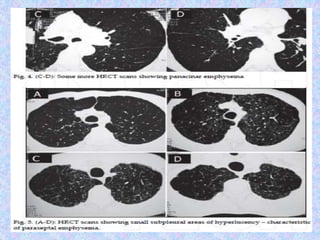

CT finding in emphysema is diagnosed by alveolar septal destruction and

airspace enlargement, which may occur in a variety of distributions.

Centrilobular emphysema is predominantly seen in the upper lobes with

panlobular emphysema predominating in the lower lobes. Paraseptal

emphysema tends to occur near lung fissures and pleura. Formation of giant

bullae may lead to compression of mediastinal structures, while rupture of

pleural blebs may produce spontaneous pneumothorax /

pneumomediastinum.

Abnormal chest X-rayfindings are usually not seen until COPD is severe. In this case, the X-ray may show: Flattening of the diaphragm, the large muscle that separates the lungs and heart from the abdominal cavity. Increased size of the chest, as measured from front to back. A long narrow heart. Abnormal air collections within the lung (focal bullae). On the lateral radiograph, a "barrel chest" with widened anterior-posterior diameter may be visualized. The "saber-sheath trachea" sign refers to marked coronal narrowing of the intrathoracic trachea (frontal view) with concomitant sagittal widening (lateral view). CT finding in emphysema is diagnosed by alveolar septal destruction and airspace enlargement, which may occur in a variety of distributions. Centrilobular emphysema is predominantly seen in the upper lobes with panlobular emphysema predominating in the lower lobes. Paraseptal emphysema tends to occur near lung fissures and pleura. Formation of giant bullae may lead to compression of mediastinal structures, while rupture of pleural blebs may produce spontaneous pneumothorax / pneumomediastinum.